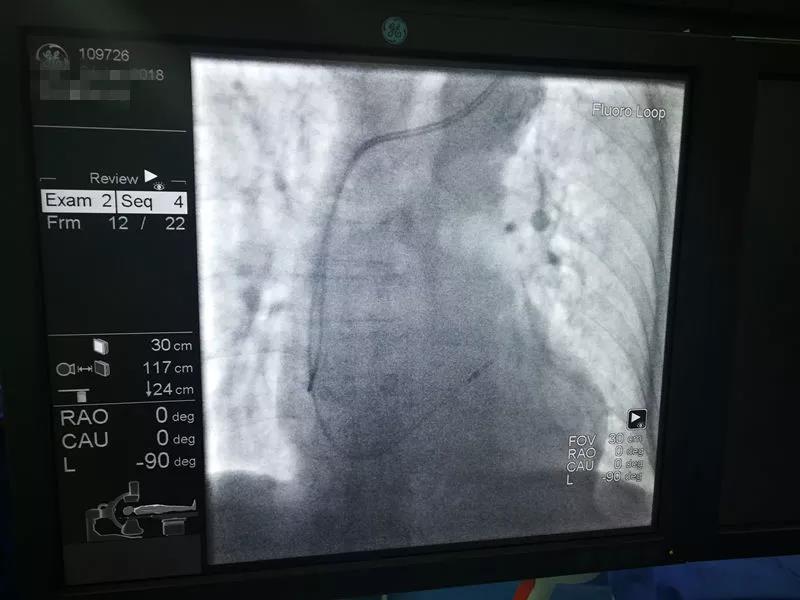

图为郭涛主任、刘可医生在为患者进行手术

内科管委会执行主任、心律失常中心执行主任郭涛教授介绍“患者为95岁男性,头晕1年加重2月入院,入院完善相关检查后、诊断为“窦房结、房室结双结病变,间歇III°传导阻滞,老年性脑萎缩”,既往曾有晕厥史。此次入院检查还发现了患者存在“冠心病,三支病变并斑块破裂”情况。由于患者冠脉病变时间长,已形成大量侧支循环,加之患者年龄大,病情重,手术当中并发症风险高,经心律失常中心专家们集中讨论以后,决定先予患者行心脏永久起搏器值入术,在保障患者心律之后,择期再行冠脉支架介入手术,手术历时约50分钟顺利完成。

此次手术在医院心律失常中心、介入中心、心脏外科的积极准备与默契配合下,仅用时50分钟就完成了手术全部过程,术后起搏器各项参数指标满意,术口恢复良好。此次介入手术的实施,为我院心律失常介入诊疗史中,创下了最高龄手术患者的记录。